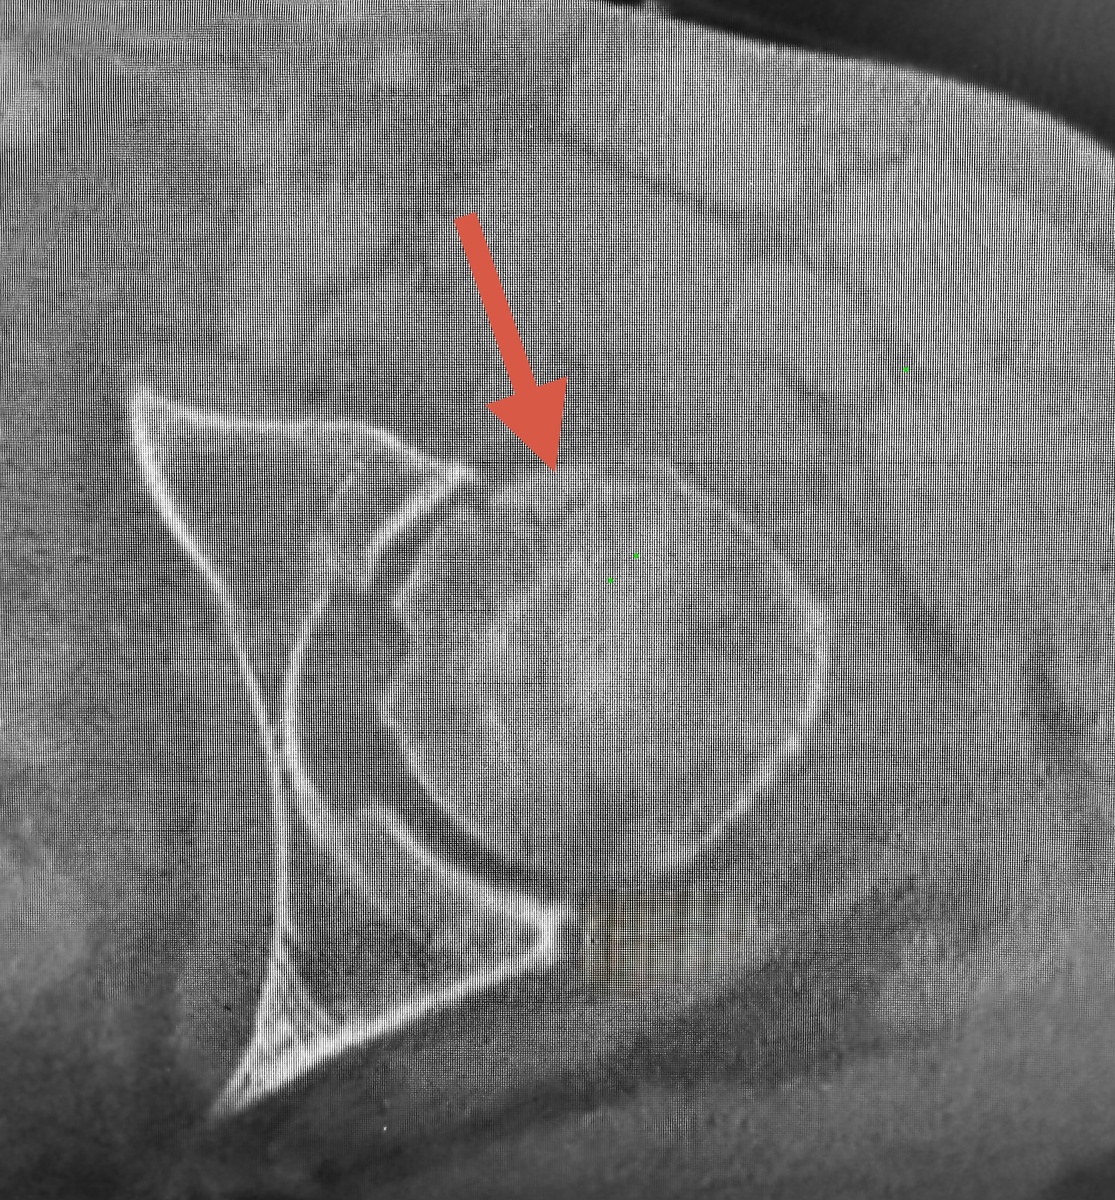

Потом боль вернулась, на компьютерной томограмме - признаки начавшегося некроза, отслойка хряща в переднем отделе головки.

Фрагмент хряща с костью

На 3D тоже хорошо видно